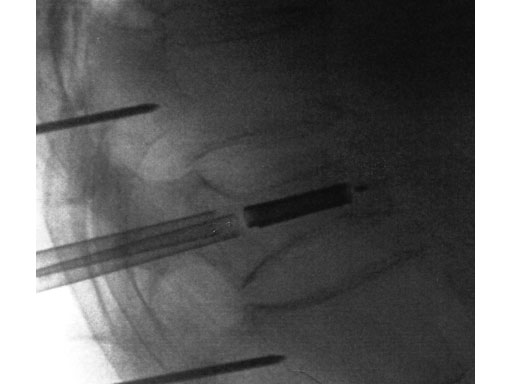

A 78-year-old man with back pain after a simple fall. An MRI showed a subacute fracture with a collapsed vertebral body of L1. A VB S was used for height restoration. The patient was pain-free immediately after the intervention.

Fig 1-4 Intraoperative images.